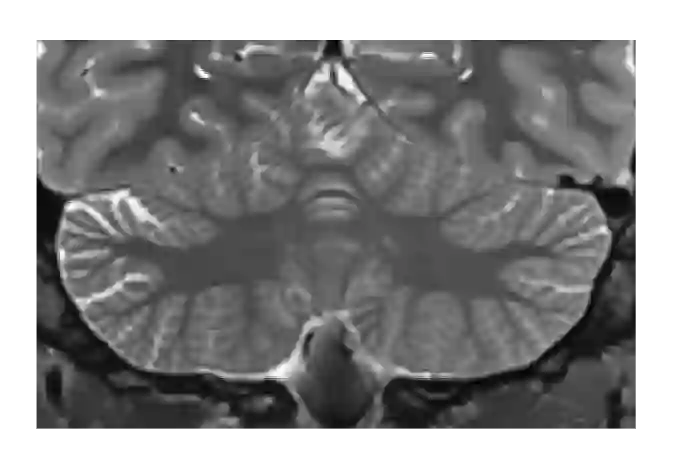

This paper introduces a novel multimodal and high-resolution human brain cerebellum lobule segmentation method. Unlike current tools that operate at standard resolution ($1 \text{ mm}^{3}$) or using mono-modal data, the proposed method improves cerebellum lobule segmentation through the use of a multimodal and ultra-high resolution ($0.125 \text{ mm}^{3}$) training dataset. To develop the method, first, a database of semi-automatically labelled cerebellum lobules was created to train the proposed method with ultra-high resolution T1 and T2 MR images. Then, an ensemble of deep networks has been designed and developed, allowing the proposed method to excel in the complex cerebellum lobule segmentation task, improving precision while being memory efficient. Notably, our approach deviates from the traditional U-Net model by exploring alternative architectures. We have also integrated deep learning with classical machine learning methods incorporating a priori knowledge from multi-atlas segmentation, which improved precision and robustness. Finally, a new online pipeline, named DeepCERES, has been developed to make available the proposed method to the scientific community requiring as input only a single T1 MR image at standard resolution.